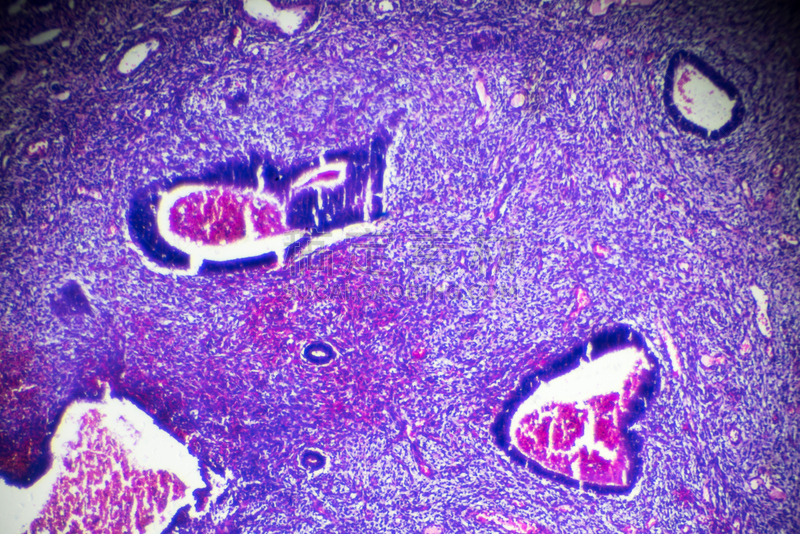

子宫解剖学中的胎儿详情